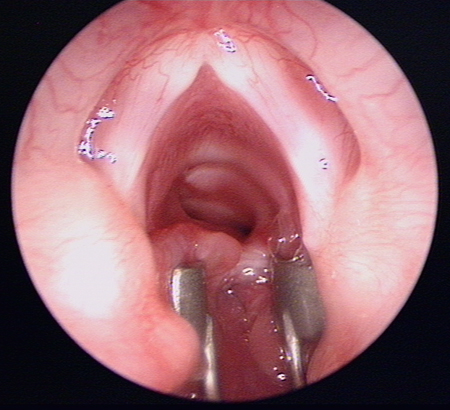

Laryngeal appearance after supraglottoplasty using cold steel

From the personal teaching collection of Simone J. Boardman, MBBS, FRACS (OHNS) and C. Martin Bailey, BSc, FRCS, FRCSEd